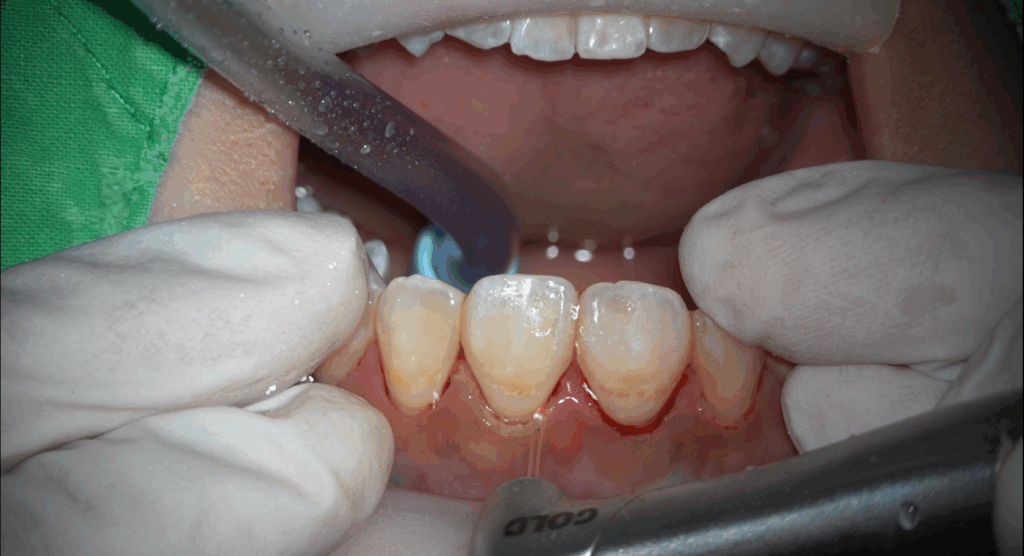

1. 水雷射牙周病治療

傳統牙周治療仰賴器械進行牙根整平術,刮除牙結石和發炎組織,過程常伴隨不適。水雷射能將探頭伸入牙周囊袋,輕鬆打掉深層牙結石,氣化增生組織,直接清除並殺滅細菌。

(1) 深度清潔與殺菌

有效清除傳統方式難以清理的深層牙結石及發炎組織,同時具備良好殺菌效果。

水雷射可用於深層清潔,尤其針對傳統洗牙難以處理的深層牙結石。

(1) 清除深層牙結石

對於藏在牙肉底下的牙結石,水雷射能有效清除。

(2) 牙周清潔輔助

水雷射可配合深層洗牙,達到更徹底的清潔與殺菌效果。